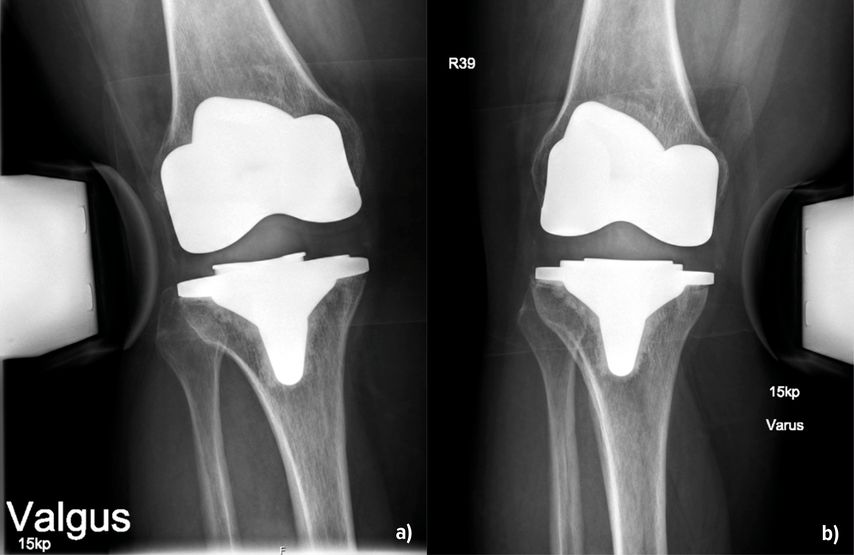

Abb. 1:Instabilität infolge eines Verschleisses. Im ap. Röntgenbild (a) sind die vermehrte laterale Aufklappbarkeit und die mediale Verschmälerung des Gelenkspaltes gut sichtbar. Das Inlay weist deutliche Verschleissspuren auf (b). Nach dem Wechsel auf ein neues Inlay in primärer Höhe ist im Röntgenbild der Gelenkspalt wieder gleichmässig dargestellt (c)

Die Instabilität von Knietotalendoprothesen beeinflusst die Zufriedenheit der Patient:innen und führt häufig zu Revisionseingriffen. In einer grossen retrospektiven Studie mit Erfassung von fast 40000 Patient:innen aus den Jahren 1996–2021 konnten Ergin et al. (2025) Risikofaktoren, welche mit einer Instabilität nach Endoprothetik einhergehen, darstellen. Dazu gehörten ein jüngeres Alter, das weibliche Geschlecht, ein Schlaganfall, tiefe Beinvenenthrombosen, Nickelallergie, Osteoporose und – überraschend – die Sklerodermie. Die Adipositas stellt demnach kein erhöhtes Risiko dar. Über die Details der Ursachen berichtet die Arbeit allerdings nicht, sondern beschreibt diese als multifaktoriell. Jedoch können die Autoren aus der eigenen klinischen Praxis berichten, dass durchaus Unterschiede in Bezug auf das Inlay bestehen. Entweder war dieses primär zu flach oder es ist zu einer Lockerung der Bänder im Verlauf gekommen. Auch der Verschleiss des Inlays über die Zeit spielt erfahrungsgemäss eine Rolle (Abb. 1). Bei der Differenzierung, welches Ausmass einer Varus- oder Valguslaxizität zu einem annehmbaren oder schlechten klinischen Ergebnis führt, fanden Mitsu-Uchi et al. (2025), dass eine mittlere Instabilität von 3–6mm im medialen Kompartiment für ein besseres postoperatives Ergebnis von Bedeutung sei. Eine straffe Implantation mit einer Instabilität von <3mm sowie Instabilitäten von >6mm führten demnach zu niedrigeren Zufriedenheitswerten bzw. Knee-Scores. Somit soll eine mittlere mediale Laxizität für ein besseres postoperatives Ergebnis sorgen, was bereits bei der Implantation Beachtung finden kann. Neben dem klinischen Nachweis ist die gehaltene Röntgenaufnahme geeignet, um den Befund zu verifizieren und zu dokumentieren (Abb.2). Bezüglich der Ursachen für Fehlschläge primärer Knietotalendoprothesen finden sich die Instabilitäten mit einer Häufigkeit von 7% bzw. 4,55% an 3. bzw. 4. Stelle. Vorwiegende Gründe für Revisionen sind hingegen periprothetische Infektionen (22,3% bzw. 47,73%), die aseptische Lockerung (20,5% bzw. 35,23%) und Bewegungseinschränkungen (5,68%) (Datta et al. 2025, Mozella et al. 2024). In einer Arbeit von Poilvache et al. (2025) wurde das Übergewicht als Risikofaktor für Komplikationen nach K-TEP untersucht. Die Hauptursachen für die initiale Revision waren die aseptische Lockerung mit 37%, die Instabilität (29%) und der Abrieb oder Osteolysen (13%). Die Arbeit erbrachte ganz klar, dass ein BMI >40kg/m2 tendenziell mit einer Reoperation korrelierte. Allerdings nicht wegen Instabilität, sondern wegen periprothetischer Infektionen, und das auch nicht signifikant. Der BMI als Ursache einer Instabilität nach Revision wurde hier ausgeschlossen. Brown et al. (2025) beschrieben ein erhöhtes Risiko mit Hinblick auf eine Revision als Folge einer Instabilität oder einer Lockerung bei Fällen, in denen die Femurkomponente grösser als die Tibiakomponente war. Die Autoren empfahlen, primär die Wahl der Prothesengrössen zu beachten, um Instabilitäten vorzubeugen. Auf die Infektionsraten und den anterioren Knieschmerz fand sich in dieser Kohorte kein Einfluss.